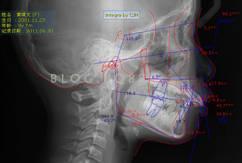

談到早期矯正,涉及到對雙期矯正概念的理解、適應(yīng)癥的把控、各種早期矯正裝置的制作與安裝、患者生長發(fā)育知識的了解等內(nèi)容。

下面這個小患者就存在需早期矯正的問題。通過早期矯正,在不長的時間內(nèi)就達(dá)到極為明顯的療效。她的情況如果等到牙齒替換完畢后再解決,矯治的難度則會非常大。